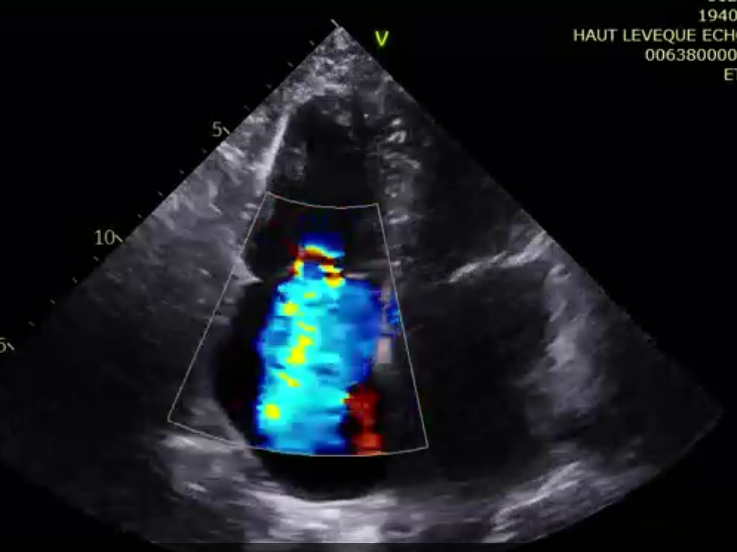

術(shù)前超聲提示極大量三尖瓣反流